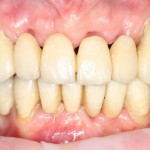

И удалили. Вместе с протезом. Через 15 минут после удаления Давид зафиксировал временный протез с опорой на импланты:

Уточню — это ВРЕМЕННЫЙ протез. При тотальном протезировании на имплантах, это почти необходимая вещь. Ибо заново настроить зубочелюстную систему, где вообще не осталось зубов, не так просто, как кажется. На это требуется время и ряд коррекций. К тому же, временный протез позволяет определить, как «работают» импланты под нагрузкой.

Таким образом, даже при таком сложном и длительном лечении, наша пациентка ни на день не оставалась без зубов и вообще не пользовалась съемными протезами. Нужно ли говорить, насколько это влияет на комфорт лечебного процесса и качество жизни?